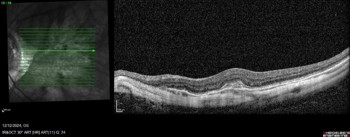

Myopic neovascularisation can present without subretinal or intraretinal fluid (see Fig 1). These type II (subretinal) lesions present as an area of thickening in the outer retina with or without minimal subretinal fluid. With high-resolution OCT imaging, active lesions will have an area of ‘fuzziness’ around the border and the external limiting membrane can be interrupted. However, these subtle signs can be difficult to detect with lower resolution OCT systems. As a result, myopic neovascularisation can be difficult to diagnose. However, there are two tips to help:

Fig 1. An example of a myopic neovascular membrane on OCT.

Notice that there is no associated subretinal or intraretinal fluid